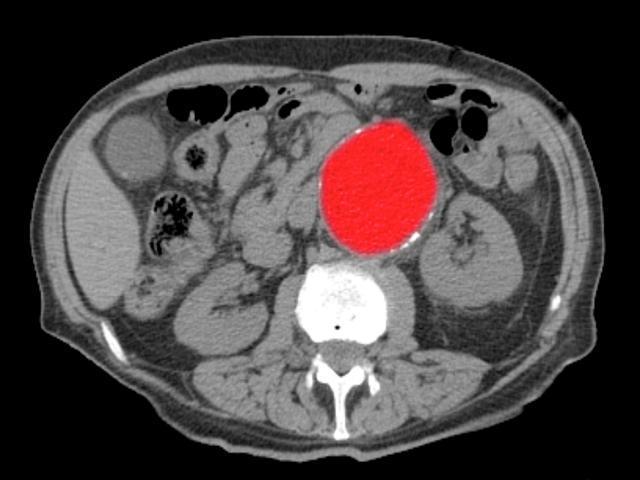

Erken ihtarlara dikkat çeken Dr. Ünal Aydın, “Aort diseksiyonu öncesinde birçok vakit belirti görülmese de birtakım hastalarda aort damarında olağandışı bir genişleme (anevrizma), duvar içinde küçük yırtıklar ya da damar içi ülserler gözlemlenebilir.

Bu bulgular, nizamlı denetimlerle erken saptanabilir. Bilhassa tansiyon hastalarında ani tansiyon yükselmeleri büyük risk oluşturur. Mevsim geçişlerinde bu risk daha da artar.” biçiminde konuştu.